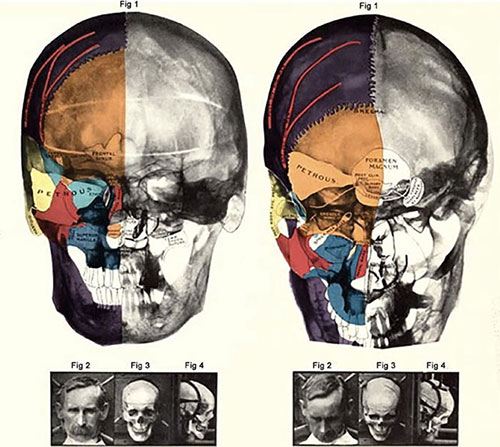

Sir Victor Horsley was the first neurosurgeon to use X-rays in neurosurgery way back in the late 19th century after their discovery.2 Soon after the discovery of plain radiograph and its utility in clinical medicine, some specialists tried to X-ray of skull of patients in order to diagnose suspected lesions in the brain.3–6 One of the most famous publications of its time was “Röntgen-diagnostik der Erkrankungen des Kopfes” by Arthur Schüller.7 The same was later translated into English under the name “Radiology of Diseases of the Head”. “Neuroradiology” was first used by Schüller describing pathologies of the brain using skull radiographs.8 The modality gained such popularity in those times that Walter Dandy and George Heuer published a paper proving changes seen in 45 patients with brain tumors out of their enlisted 100 patients (Figure 1.1).9

However, this modality had its own limitations namely long period of immobility to acquire image, soft tissue pathologies could not be detected, neoplasms without bony involvement or calcification were literally invisible. In reality, by the time actual pathologies were identified on skull radiographs, clinically, it was too late for the patient to undergo any intervention.10 Despite of the advances over the centuries, spine radiograph is still an essential part of orthopedics and neurosurgery.